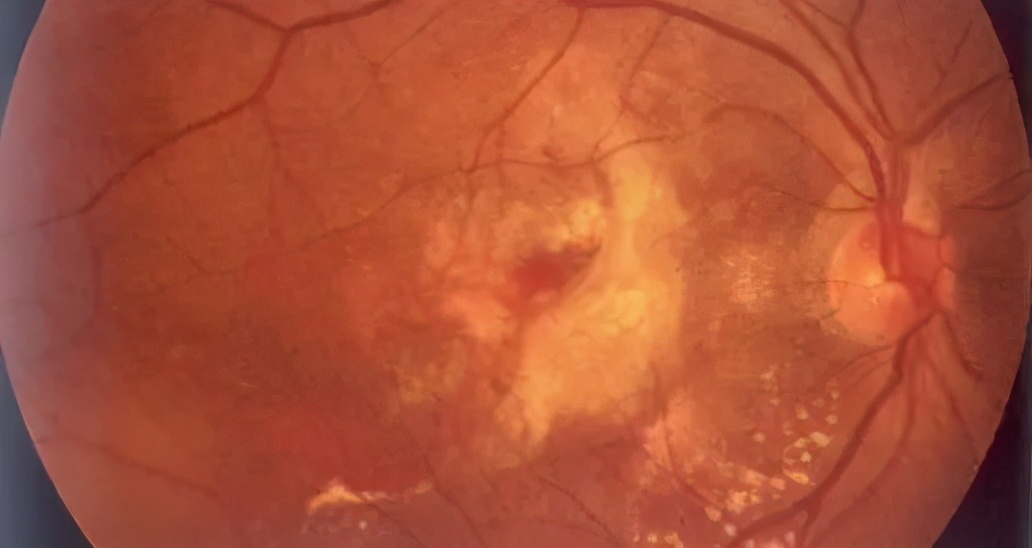

黄斑不属于“斑”的一种,它是视网膜上一个重要的生理性结构,位于视神经视盘的颞侧大概3.5个毫米偏下处。由于黄斑区的叶黄素较多且集中,所以看起来比周围的视网膜颜色暗些。

正常情况下,黄斑无法用肉眼识别,只有专业的眼科医师通过眼底镜检查或眼底照相,才能观察到黄斑的结构。

- 到医院进行眼底照相、光学相干断层扫描(OCT)、眼底荧光血管造影等相关检查。